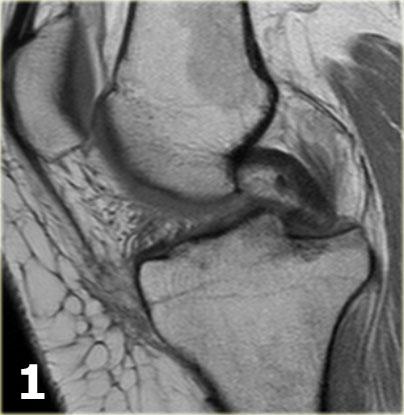

Hãy quan sát hình ảnh bên trái và cố gắng xác định vấn đề của sụn chêm này là gì.

Sau đó tiếp tục xem các hình ảnh liên tiếp tiếp theo của cùng bệnh nhân này.

Như bạn đã đoán được qua tiêu đề của đoạn này, đây là một trường hợp sụn chêm lật (flipped meniscus).

Sụn chêm lật là một dạng đặc biệt của rách dạng quai xô (bucket-handle tear).

Sụn chêm lật xảy ra khi mảnh vỡ của sừng sau bị lật ra phía trước, khiến sừng trước của sụn chêm có vẻ to hơn bình thường.